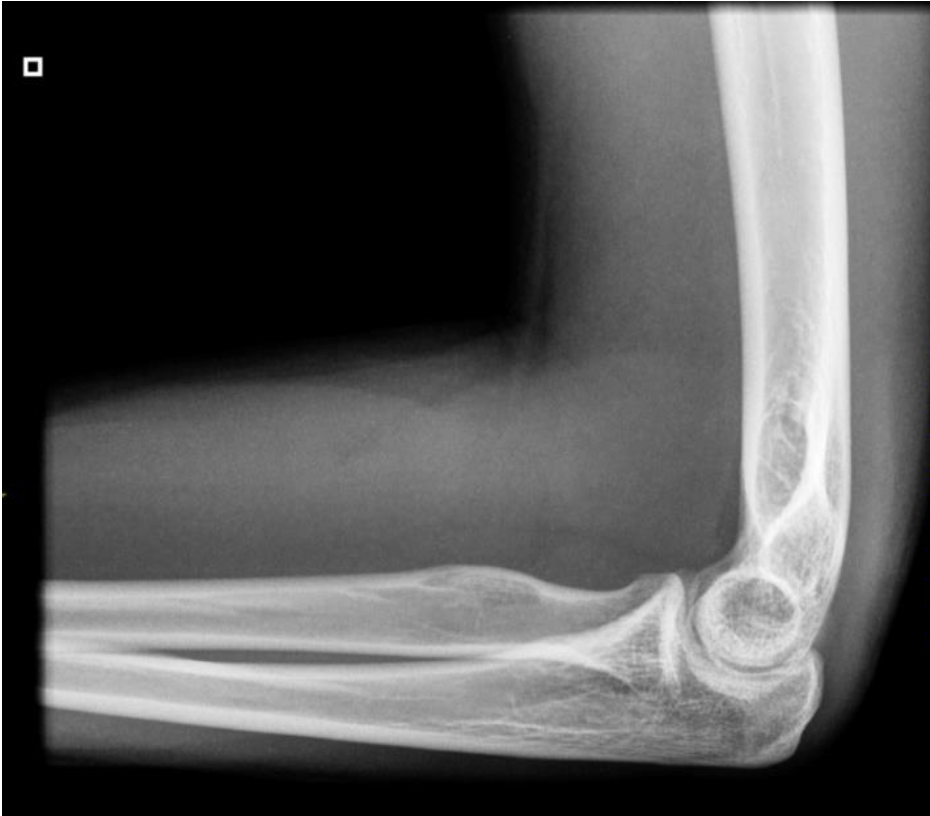

What is this view in the elbow? What views are missing?

– Lateral Flexion

MISSING:

– AP

– Medial Oblique

– +- supination or pronation AP